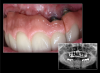

Fig 15. Smartphone dental photography can also be used in laboratory shade communication. In these images taken using MDP, the photo on the left shows value selection, while the one on the right shows chroma/hue selection.

Figure 15

Fig 16. Polarizing light filter attachments are available for several dental smartphone EALSs, such as the MDP (left) and COCO Lux (right).

Figure 16

Fig 17. Polarized shade photography is possible using the smartphone; this image was captured using MDP.

Figure 17